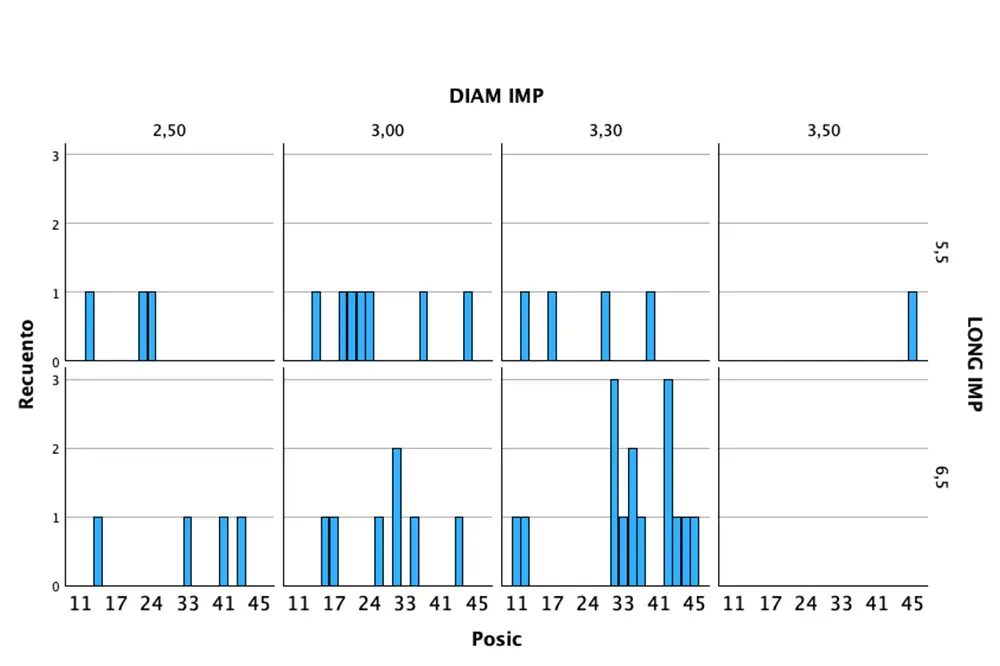

Fueron reclutados 9 pacientes en los que se insertaron 41 implantes que cumplieron con los criterios de inclusión anteriormente descritos. La edad media fue de 68,77 años (+/- 6,69) y 6 de los 9 pacientes eran de sexo femenino. De los 41 implantes, el 41,5% se insertaron en el maxilar superior, siendo la posición más frecuente para esta área anatómica la correspondiente al diente 13 (7,3%) y el 58,5% en la mandíbula, siendo la localización más frecuente en esta área para la pieza 32 (12,2%). Todas las localizaciones analizadas se muestran en la figura 1. En cuanto a las dimensiones de los implantes, el diámetro osciló entre los 2,5 y los 3,5 mm, siendo el más frecuente 3,30 mm en el 53,7% de los casos. La longitud de los implantes fue de 5,5 mm en el 36,6% y de 6,5 mm en el 63,4%. Todas las longitudes y diámetros en función de la posición del implante se detallan en la figura 2.

Figura 3. Torque final de inserción de cada uno de los implantes y densidad ósea del lecho, categorizado en función del tipo óseo.